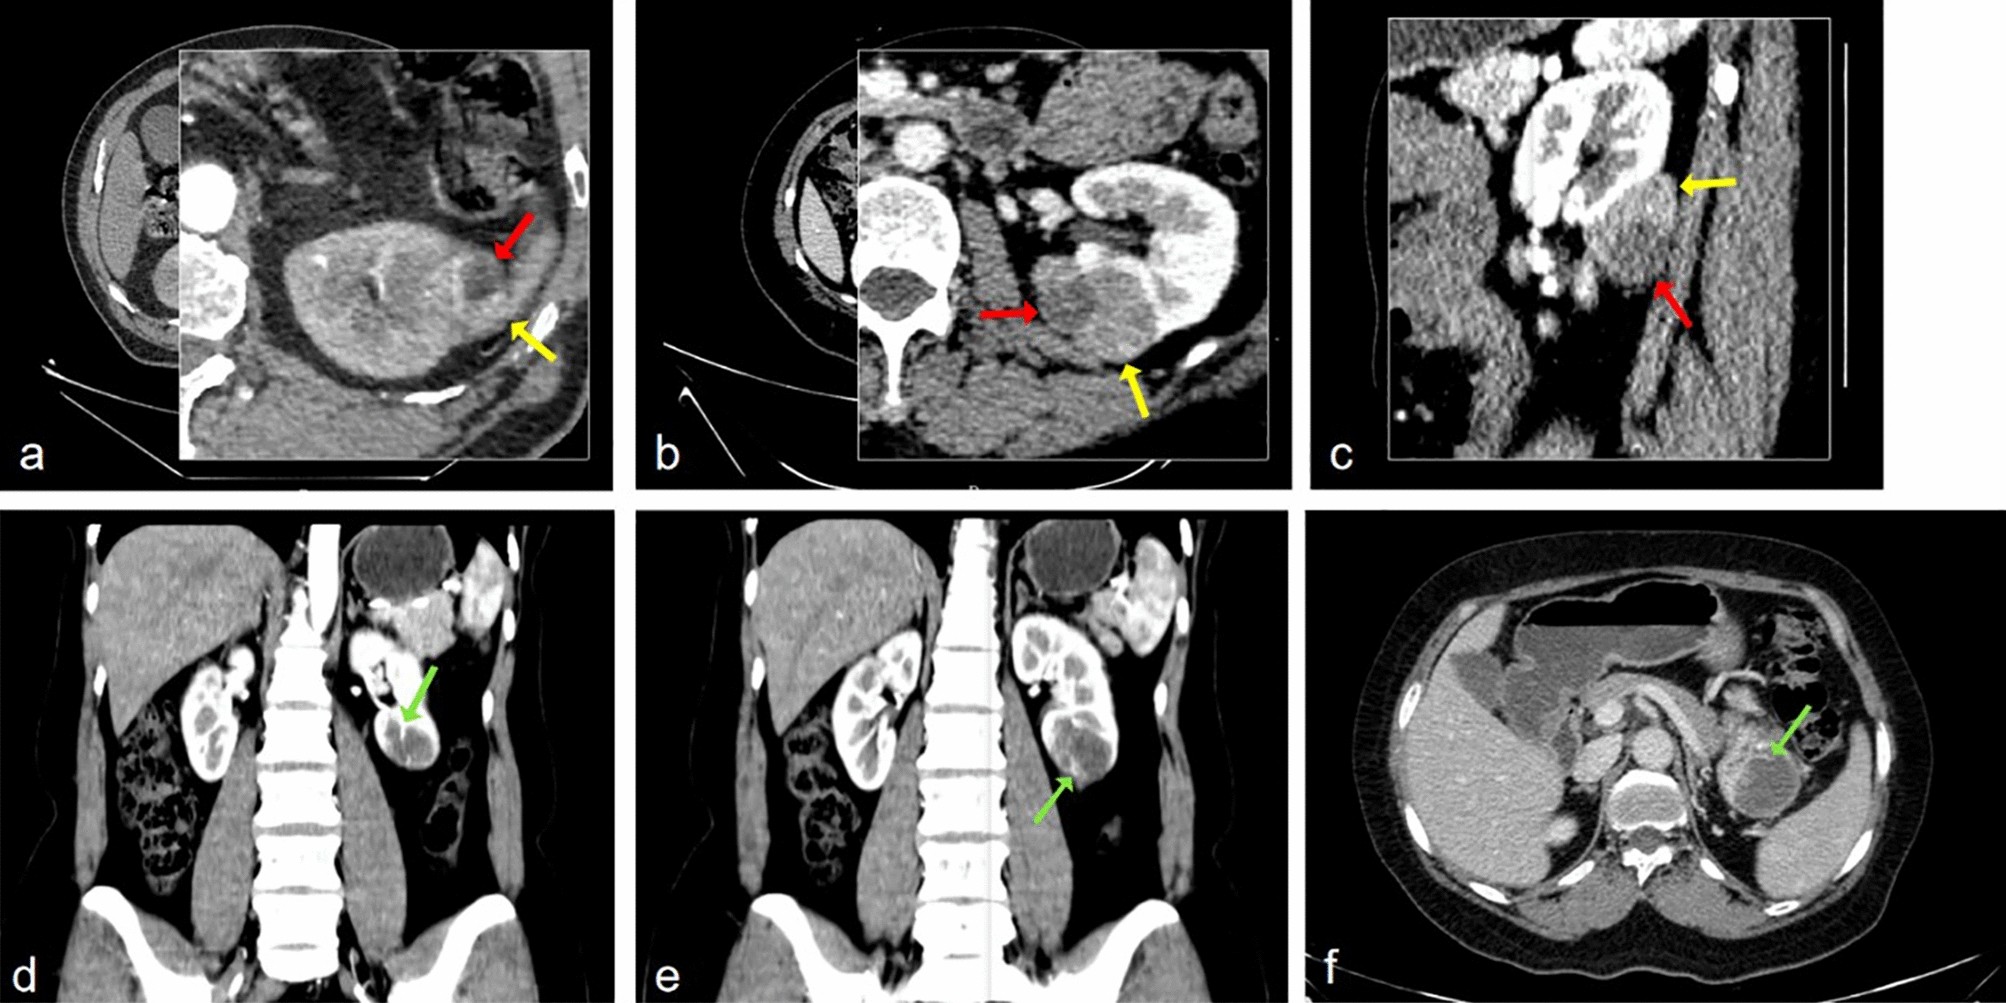

Figure 3

(a,b,c) Postcontrast CT: cystic (red arrow) and solid (yellow arrow) components of unilocular cystic clear cell RCC. (e,f,g) irregular internal structures (green arrow) in the unilocular cystic papillary RCC.